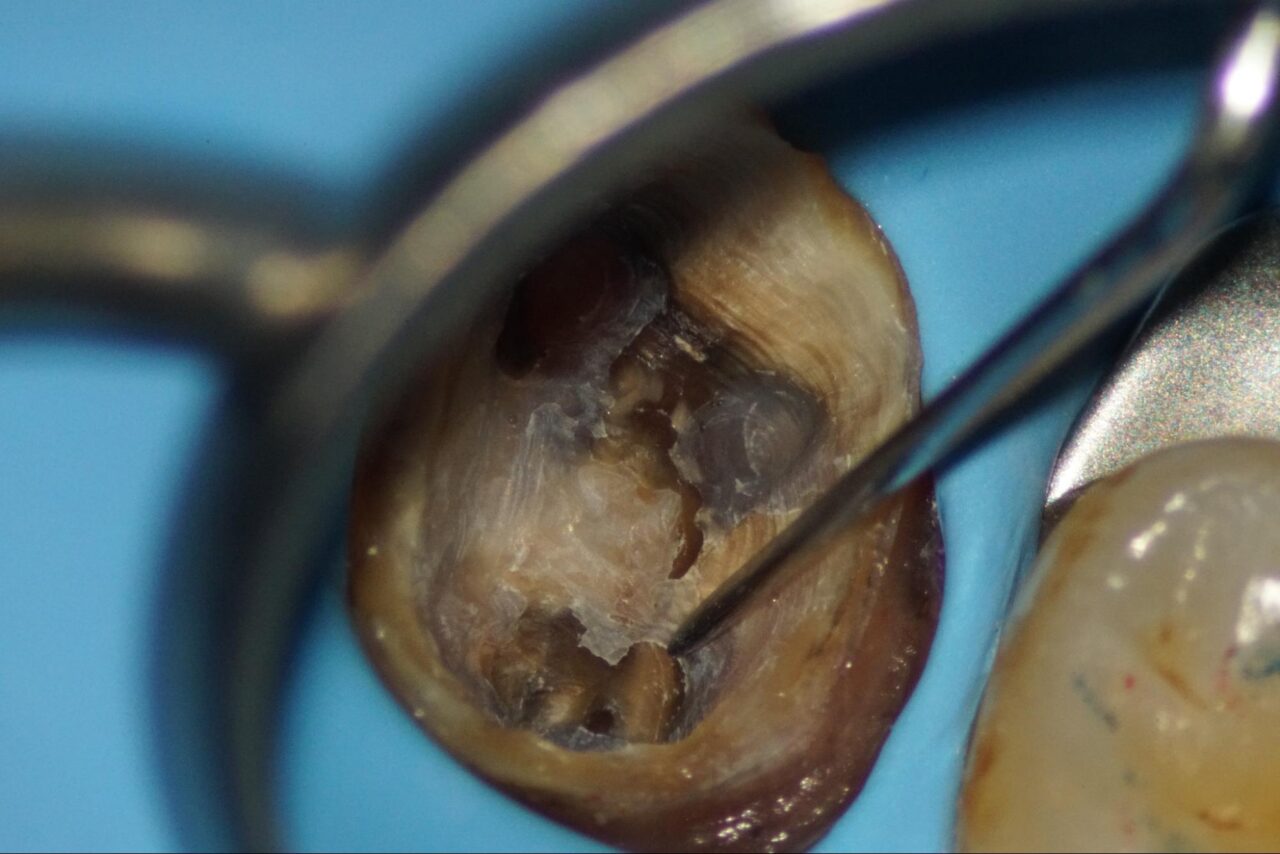

根管口にまだ、レジンや感染歯質が残っています。

感染部、虫歯の部分が緑色の染まる検知薬を何度も用いて、感染歯質を完全に除去を行います。

そうすると事前に予測していた通りにクラックラインが視えてきました。

根尖部に残っている以前の根管充填材を確実に除去します。

クラックラインが明確になってきました。

レジンで隔壁を作り、初回の感染根管治療は終了です。

次回根管内に以前の根管充填材が除去できている事を確認して、根管洗浄をして根管充填を行います。